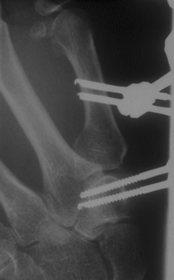

Offene Reposition und Stabilisierung

mit Schrauben

| Gelingt die geschlossene Repostion nicht, so muß

offen reponiert werden. Dies Verfahren aber ist besonders schwierig,

da das Fragment nicht ideal darstellbar ist. Auch in der Hand des

Erfahrenen ist nicht immer optimale stufenfreie Stellung erzielbar.

|